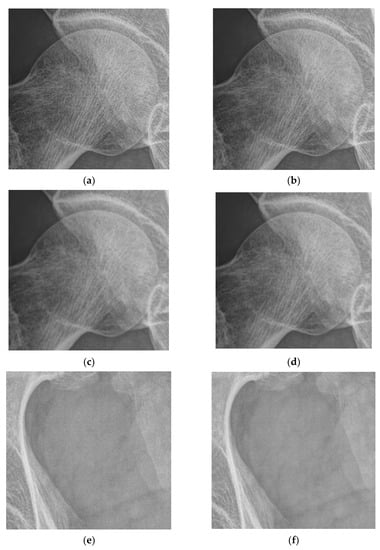

4.2. Simulations for Multiscale Noise Reduction in DR Images